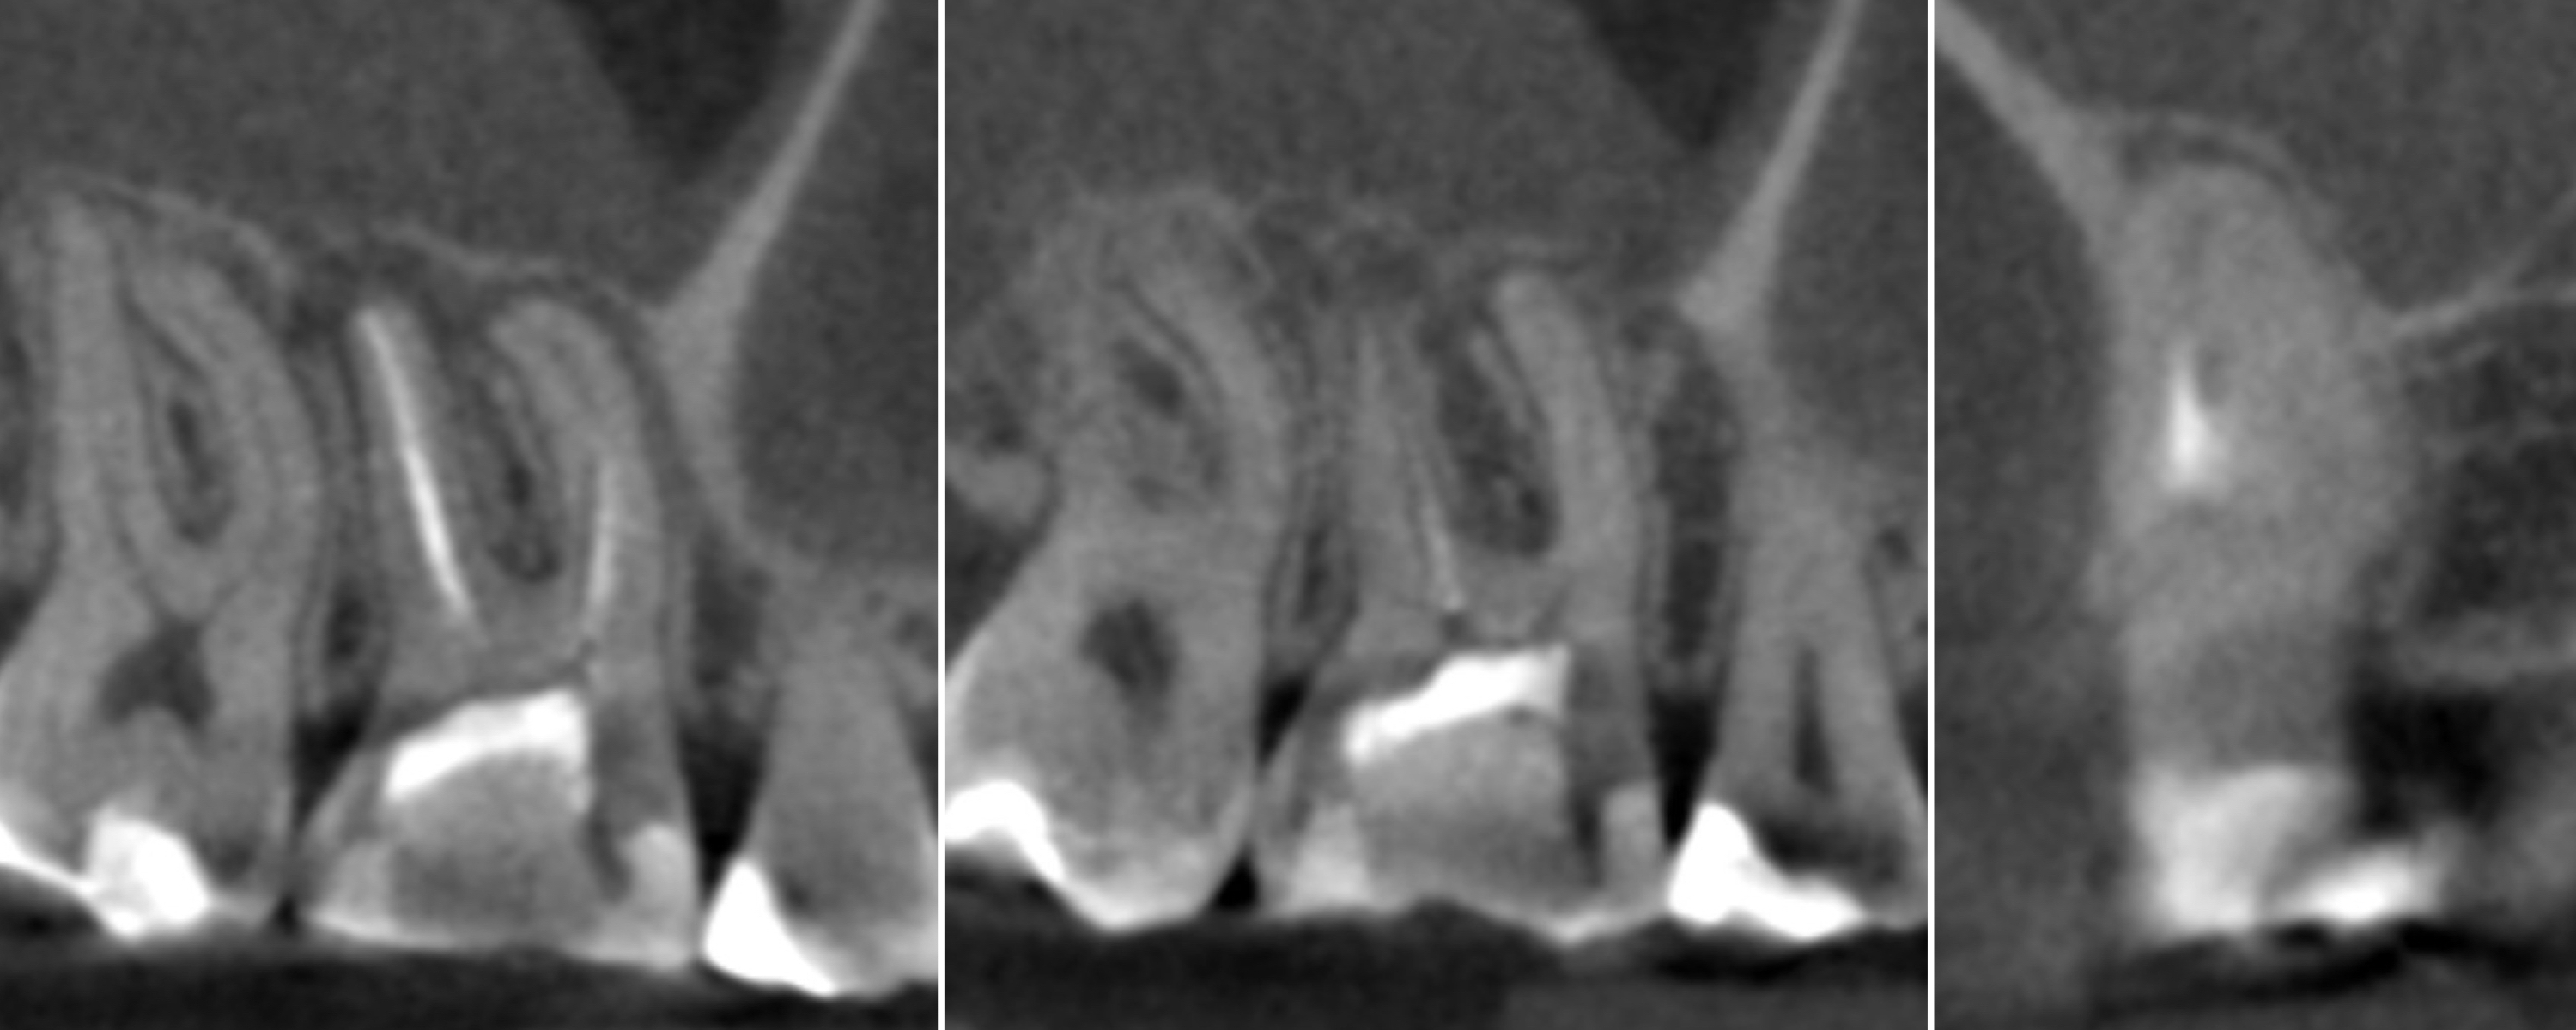

To confirm that the mesial root had been filled properly, the patient was referred for a CBCT scan. The examination revealed that the MB2 canal had been filled with the sealing material and that there was an isthmus between the MB1 and MB2 canals in the apical third of the root and two separate portals of exit (Fig. 14). The tooth was restored with composite resin, and the patient was referred for an indirect restoration with cusp coverage and scheduled for a recall appointment in six months.

At the recall appointment, the CBCT examination found no signs of inflammation. The tooth was asymptomatic, and the Schneiderian membrane was not enlarged (Fig. 15).

Fig. 14

Figs. 15a & b